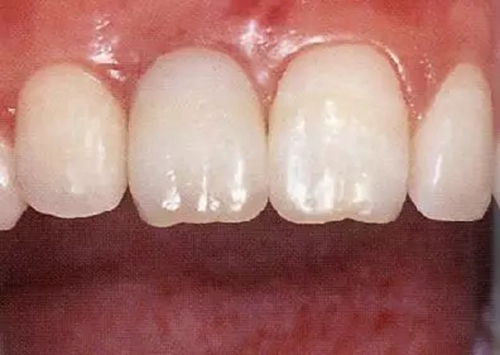

▲圖44-15,16

佩戴最終修復(fù)體時(shí)的正面口內(nèi)照和X光牙片。取得了很好的美觀狀態(tài)。

▲圖44-19,20

初診時(shí)和佩戴最終修復(fù)體時(shí)的狀態(tài)。適當(dāng)修正牙冠形態(tài)后,恢復(fù)了前牙的美觀性。

▲圖44-21

6年后的狀態(tài)。